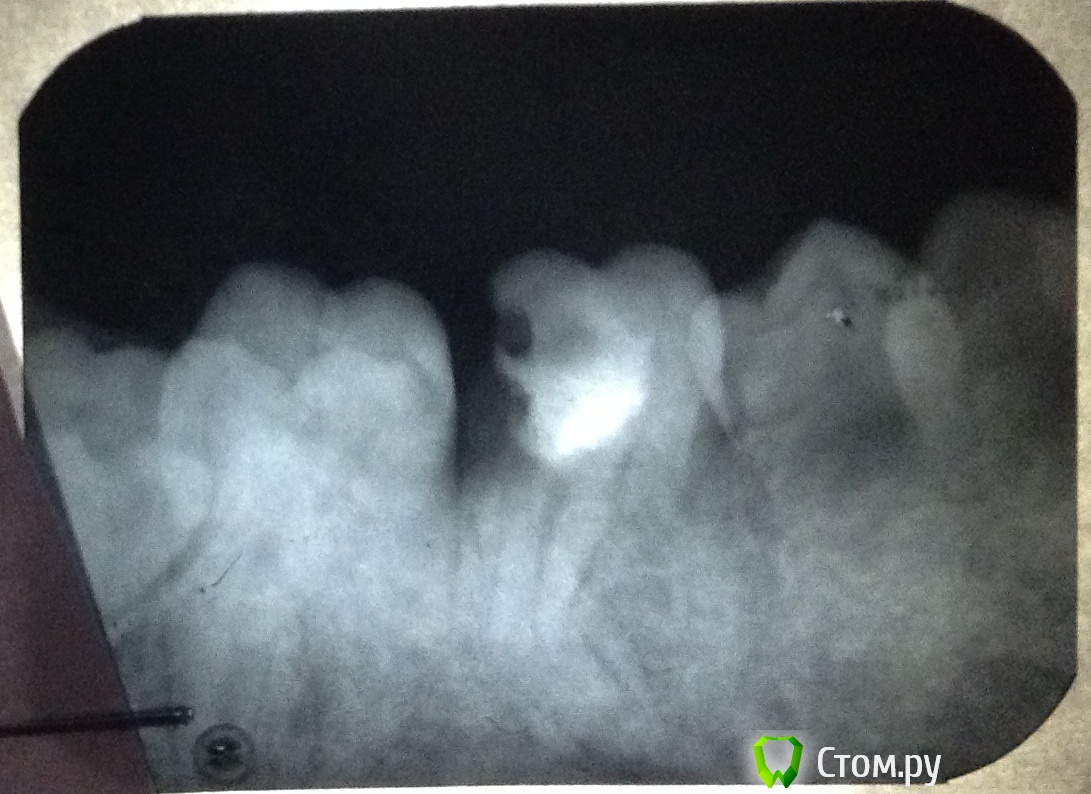

and13 Опубликовано 27 мая, 2014 Поделиться Опубликовано 27 мая, 2014 Приветствую. Ситуация такая: давно лечил зуб 36. Пломба и вроде каналы (не знаю точно насчет каналов, снимки прилагаю)Недавно откололось пломба, пошел к врачу. Она посмотрела снимки и сказала что тут ничего сделать нельзя совсем, зуб сгнил внутри якобы, только удаление зуба и ставить имплант. Направили к хирургу. Мне совсем не хочется удалять зуб. Вроде оставляют корни и ставят коронку или еще что? Посмотрите, выскажите свои предположения что можно сделать, жду любых советов. Спасибо п.с. качество фото может быть не очень, завтра могу приложить новые 1 Ссылка на комментарий

art700 Опубликовано 27 мая, 2014 Поделиться Опубликовано 27 мая, 2014 По снимкам зуб на удаление. А так снимки нужны получше Ссылка на комментарий

Scrabble Опубликовано 27 мая, 2014 Поделиться Опубликовано 27 мая, 2014 Дистально(сзади) зуб разрушен сильно-не восстановить. Ссылка на комментарий

and13 Опубликовано 27 мая, 2014 Автор Поделиться Опубликовано 27 мая, 2014 Сделал фото на фоне монитора. Вроде получше видно. П.с. делают же вроде коронку на штифт, чтобы не удалять зуб? Или может что-то еще подскажите?Корни то целые? Ссылка на комментарий

red_butler Опубликовано 27 мая, 2014 Поделиться Опубликовано 27 мая, 2014 Удалять Ссылка на комментарий